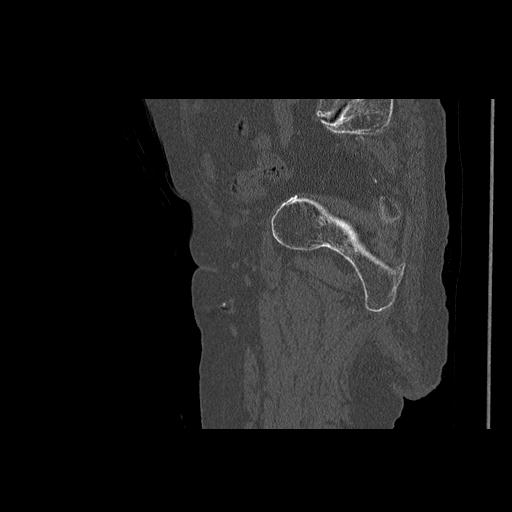

102803 1/12(キウスなし) 1/27 左下腿 4R 30歳女性 左脛骨軸内釘